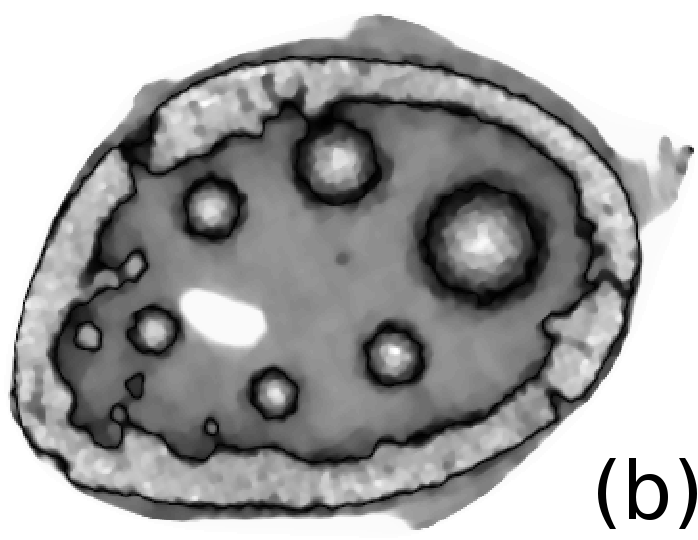

Reconstructed images are presented in Fig. 4. Since CGLS-TV- reconstruction might look more appealing than CGLS-EL we also show the surface representations of reconstructed images (see Fig. 5) and horizontal middle cross-sections (see Fig. 6).

One can notice that CGLS reconstruction is very noisy. CGLS-TV method better suppresses noise, however smooth features are strongly affected by the “staircasing” effect. CGLS-TV- method provides reconstruction with smoother features and CGLS-EL method resolves smooth features even better (e.g. cone-shaped parabola). Although CGLS-EL method performs very well for smooth objects one can notice the wave-like variations of intensity in the background and also at the top of the rectangle (see Fig. 6). This issue can be explained by the properties of our regularizer, in contrast to TV, our penalty does not seek the sparsest solution and does not penalize strongly (pushing to the constant value) a small intensity perturbations. The EL term tends to preserve all sharp edges while uniform noise is smoothed isotropically with the Laplacian. In Fig. 6 one can see that the CGLS-EL method provides better recovery of smooth features while slightly higher (compare to TV and TV-) perturbations visible in uniform areas (the top of the rectangle), however, the edges of the rectangle are defined sharper with the EL penalty.

In Fig. 10 and 11 one can notice that the BR is very smooth for TV and TV- penalties and some long-wave oscillations can be seen in the reconstructed image with EL penalty. This result corresponds to the expected behaviour of the EL penalty. We note here that the phantoms background (see Fig. 7) is not as flat as TV and TV- penalty recovered it. Furthermore, a small size dot-like feature (approximately in the centre of the phantom) is almost smoothed out with TV and TV- recovery. However, it is visible and well recovered with EL penalty. The sharp features, overall, are reconstructed very well with MLEM-EL method and seem even sharper compare to other methods (see the bone outer rim in Fig 10).